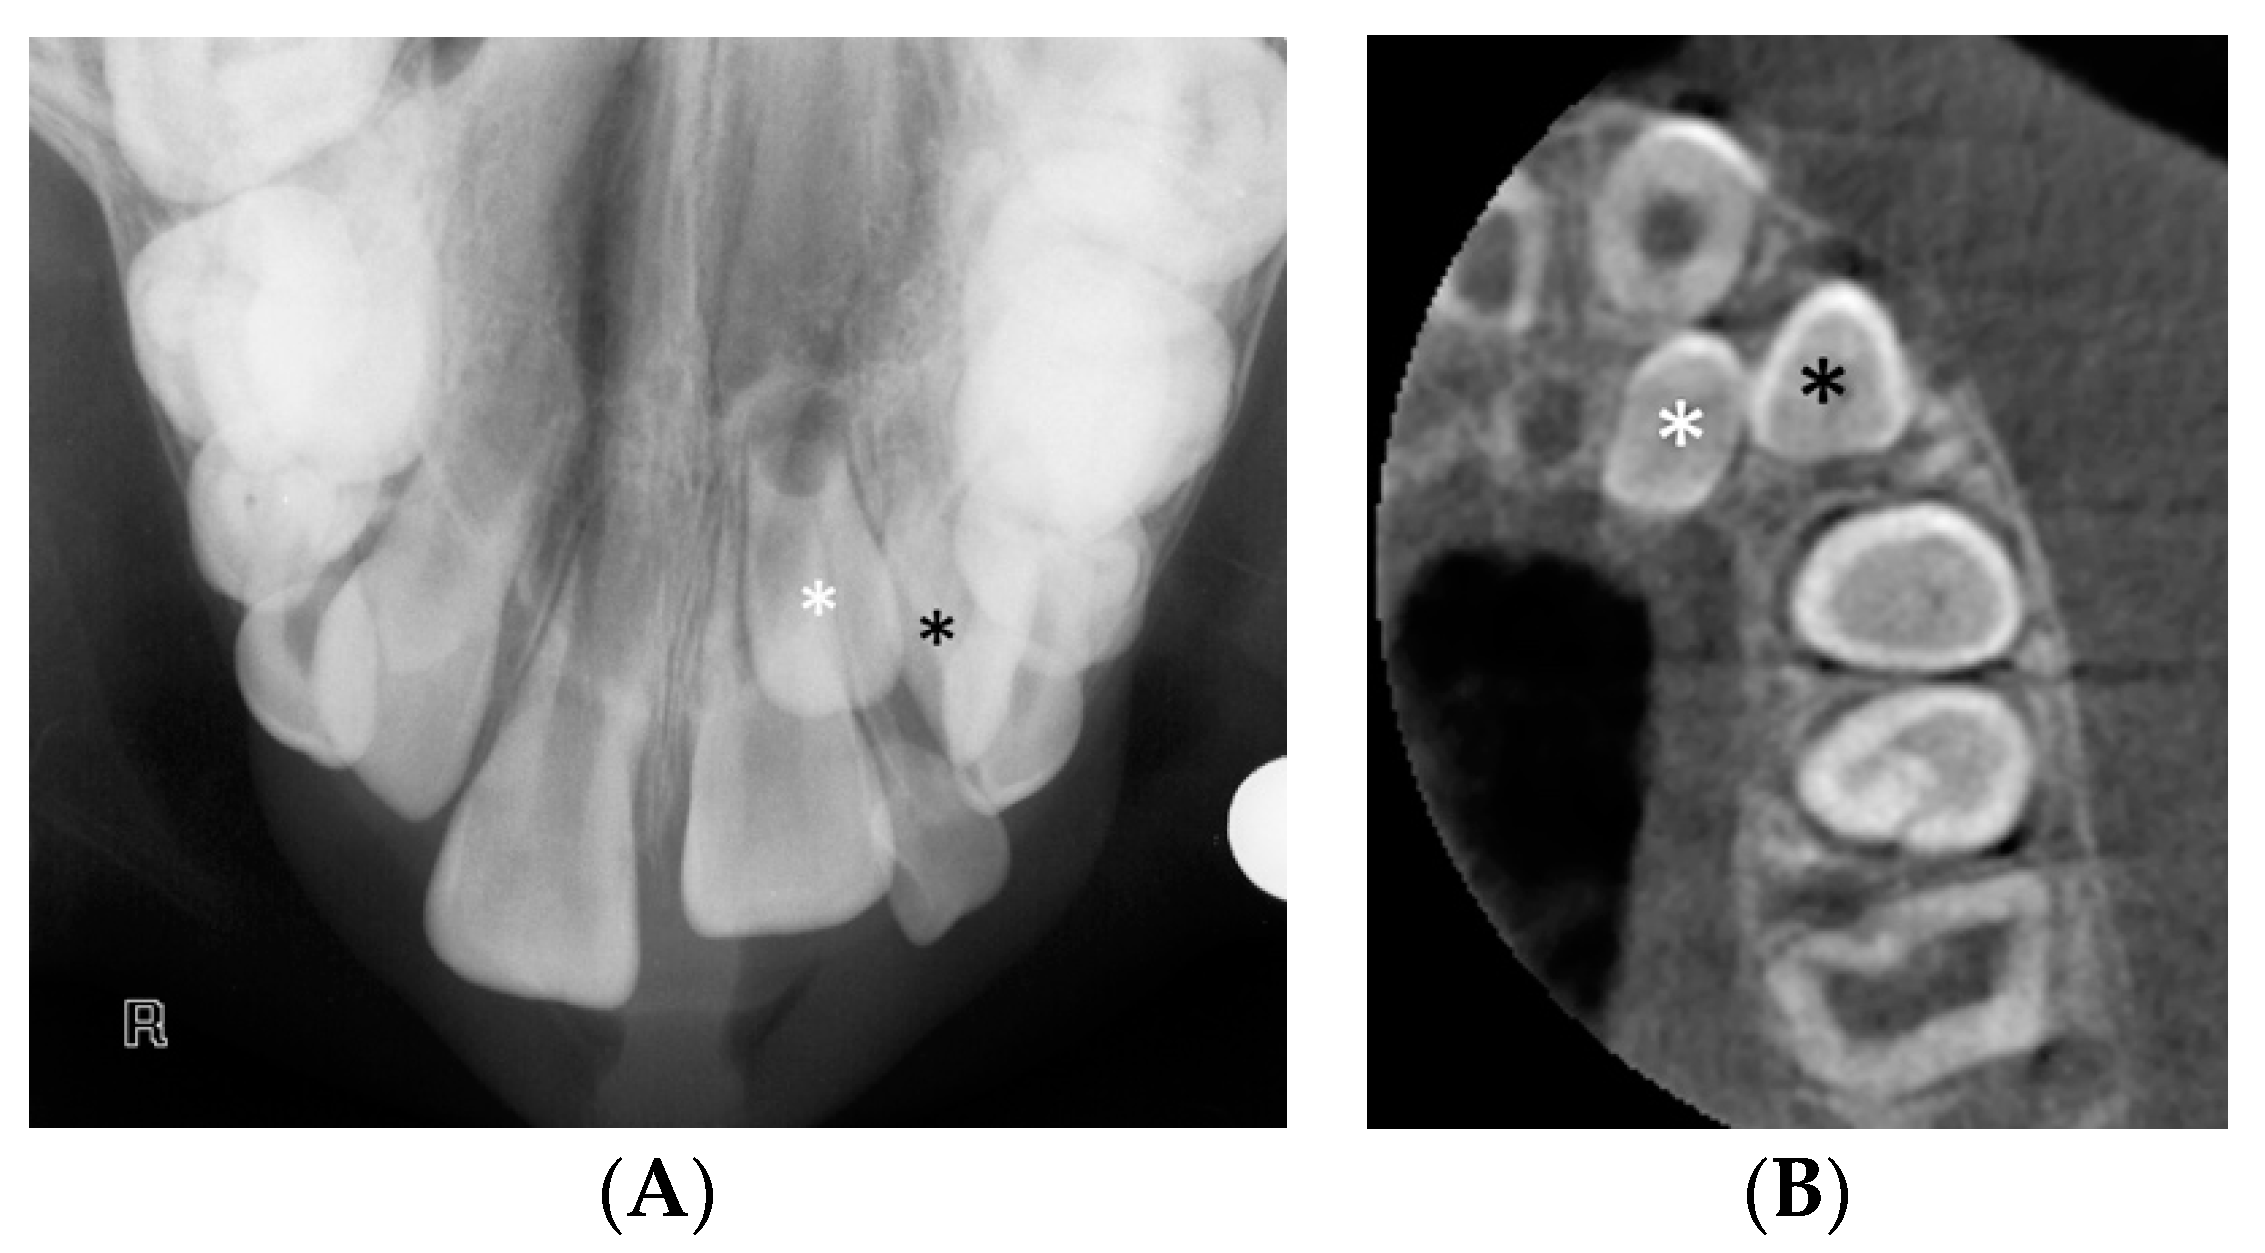

Figure 1 represents an impacted canine case that was referred for CBCT to assess localisation and the extent of root resorption after the panoramic radiographic revealed root resorption of the upper right central incisor. The provisional treatment plan, which suggested the surgical exposure of the upper right canine for orthodontic alignment into the upper right central incisor position, was altered following the acquisition of additional information from the CBCT. The CBCT revealed the exact inclination of the long axis of the canine, the extent and location of the root resorption of the upper right central incisor and of the upper right lateral incisor. Due to the unfavourable oblique position of the upper right canine, the treatment plan was revised for its surgical removal. The upper right central incisor was deemed poor prognosis due to the significant resorption visualised in the apical root third with pulpal involvement and was to be closely monitored alongside the upper right lateral incisor.

Figure 1.

(A) Panoramic radiograph showing bilateral ectopic and impacted canines. (B) Three-dimensional (3D) segmented reconstruction showing the position of the upper right ectopic canine localisation and associated resorption of the upper right central incisor (©DentsplySirona-Simplant® Pro).